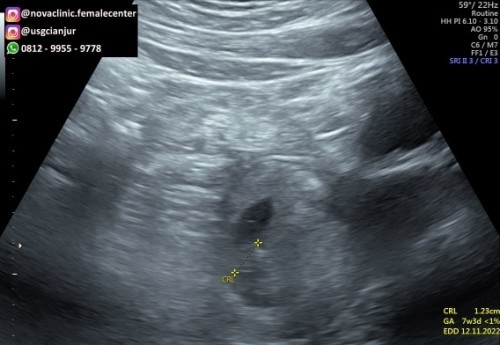

Bun mau tanya adakah bunda2 yang pas usg pertama UK udh 5w5d dan masih berupa kantong janin disuruh datang lagi 2 minggu kemudian, secara logika usg pertama 5w5d klo 2 minggu kemudian berarti UK di 8w lebih brp hari tapi waktu usg kedua baru 7w3d, sedangkan itungan diaplikasi harusnya UK 8w1d apa itu normal ya? Cuman udh keliat janinnya tapi gak begitu jelas gambarnya tpi blm ada detak jantung bun. Rasa seneng, takut, was2 campur aduk soalnya ini kehamilan kedua setelah kehamilan pertama keguguran karena BO bun 😣😣 #bantusharing #seriusnanya #ingintahu #pleasehelp #firstbaby #firstmom